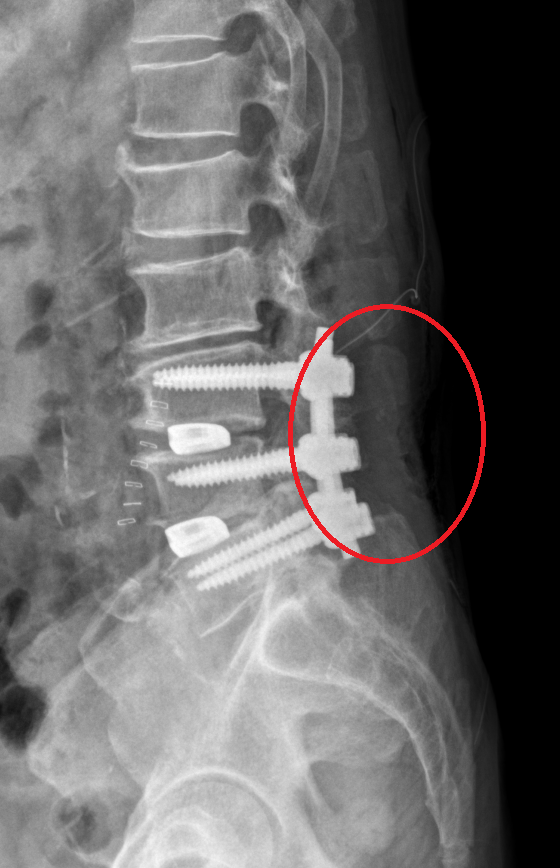

사진은 total laminectomy를 했다. 동그라미 안쪽에 아래를 보면 아래는 뼈가 없다.

total laminectomy 를 할 경우 lamina와 spinous process를 모두 제거한다.